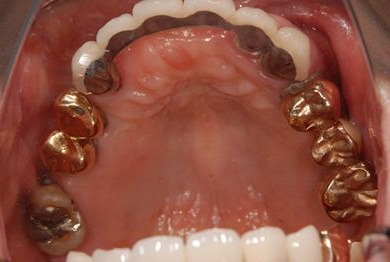

インプラントの症例写真 IMPLANT

| 治療内容 | インプラント8本(抜歯即日スピードインプラント、サイナスリフト)、ハイブリッドセラミック8本 | ||||||||||||||||||||||||||||||||